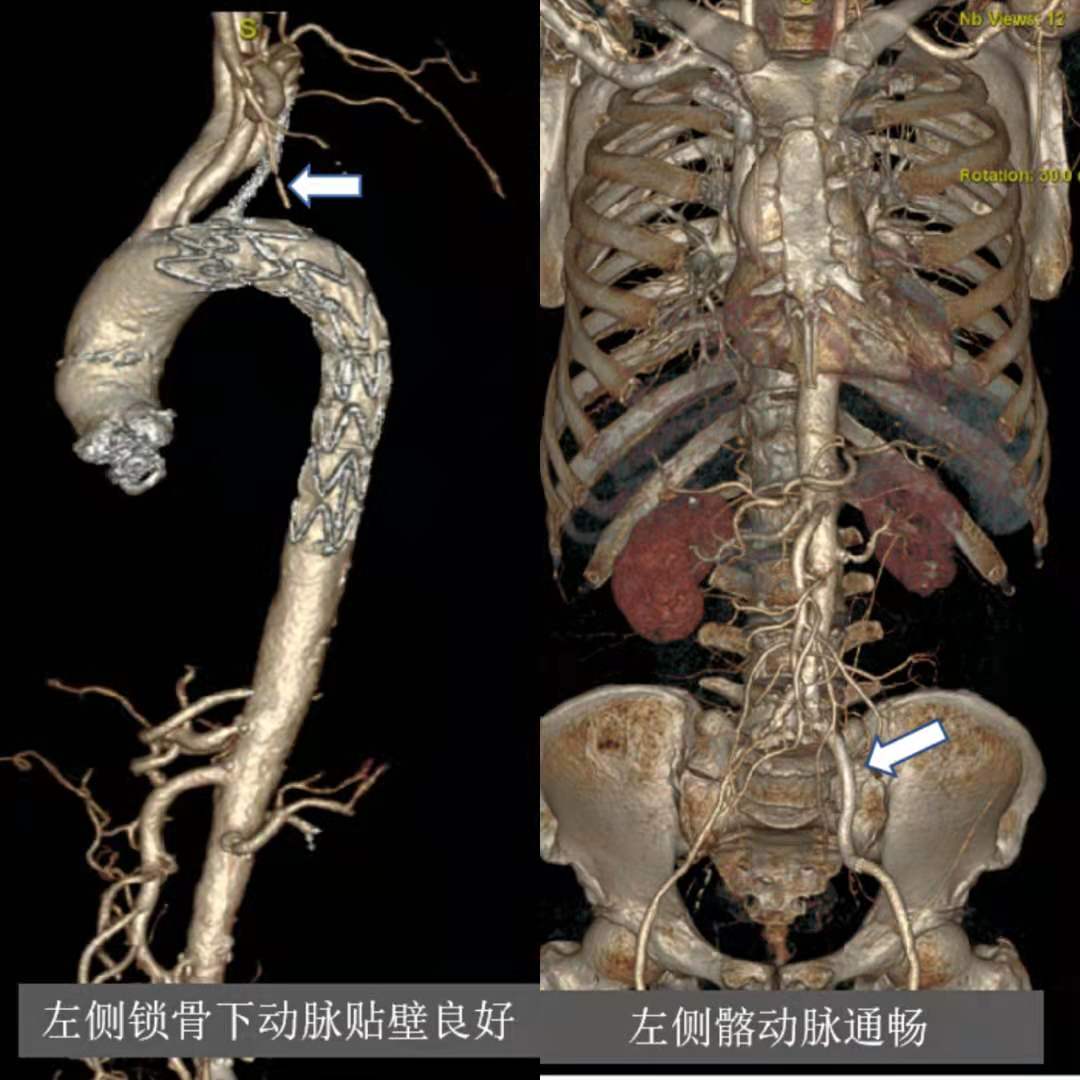

为此,张大爷找到独墅湖医院介入与血管外科张喜成主任,医生们根据影像,认为主动脉弓部穿透性溃疡最危险,很容易导致夹层或破裂引起生命危险,另外左锁骨下动脉、髂动脉均完全闭塞,这些都给治疗上带来挑战。经研究讨论后医生们决定同期解决多处血管问题。手术在我院先进的复合手术室进行,张主任、黄献琛博士和顾铖涛医师密切配合,术中因锁骨下动脉闭塞段的钙化很严重,很难开通,但他们艺高胆大,采用双向穿刺技术成功开通血管,然后用覆膜支架覆盖主动脉的溃疡,但由于溃疡距离左锁骨下动脉较近,故他们采用“浮潜”技术,既盖住了溃疡又保证分支血管的畅通。最后他们又成功开通了闭塞的左髂动脉,并植入血管支架解除了狭窄。

术后第二天张大爷就能下床活动,术后5天患者复查CT提示支架通畅,在位良好,支架贴壁紧合。